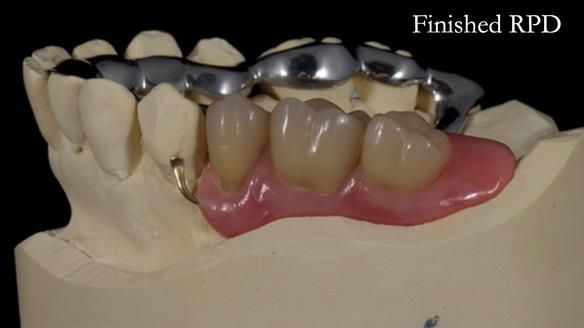

Welcome to Newsletter 64. I'll walk you through the process of providing a Mk 2 metal-based partial denture (RPD), for Ian a retired Veterinary Surgeon aged 78. The RPD was made at an increased vertical dimension and acted as an occlusal stabilisation splint - reducing the wear and bite force on the remaining natural teeth.